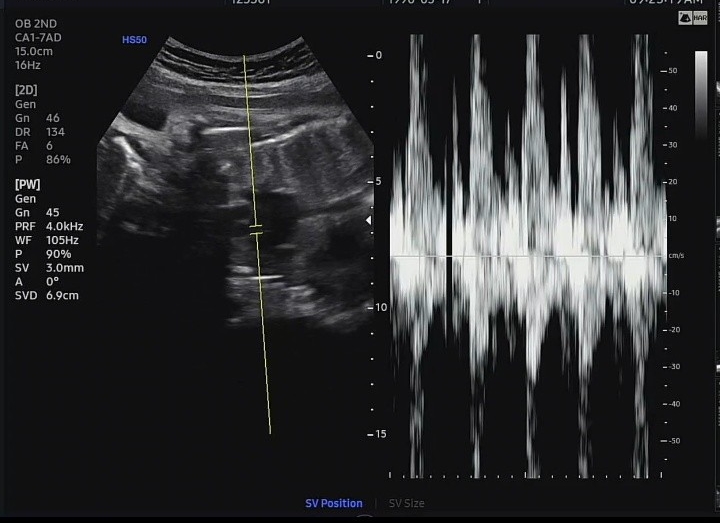

임신 32주차 - 초음파, 소변검사

#임신9개월 #임신32주차 #임신후기 어느덧 임신 후기 9개월차에 접어들었다 첫째때보다 시간이 안가는 느낌...